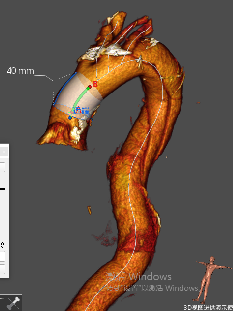

★ 病例3:弓部动脉瘤伴大量附壁血栓

该病例动脉瘤内有大量附壁血栓,一旦术中血栓脱落,可能导致脑梗死或者栓塞。

主体支架顺利通过主动脉弓准确定位释放,各分支依次延导丝进入内嵌通道后释放。治疗效果良好,没有任何卒中和栓塞。